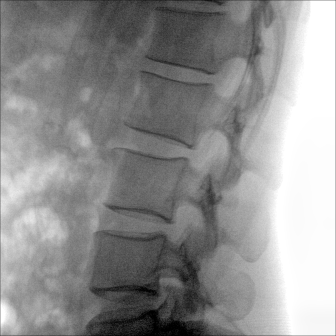

大尺寸動態平板探測器,高DQE、低噪聲、圖像清晰。采用多分辨率圖像增強處理技術,不同部位不同圖像處理算法,滿足客戶多樣化的需求。

采用智能變頻脈沖透視技術,優化圖像質量的同時降低輻射劑量,呵護醫患健康